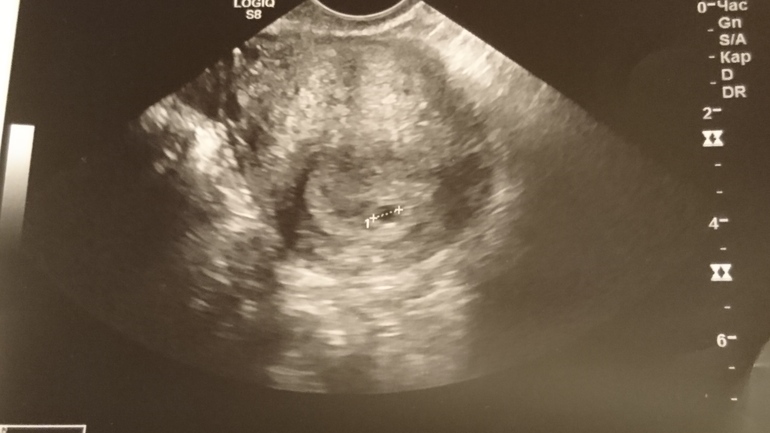

Сегодня, 24 числа поехала на узи. А там меня не обрадовали. Акушерский срок считают от 1 дня месячных. Это 5н и 6д. А на узи, плодное яйцо в полости матки. Размер 5 мм. Соответствует 2 эмбриональным неделям. Это очень мало.